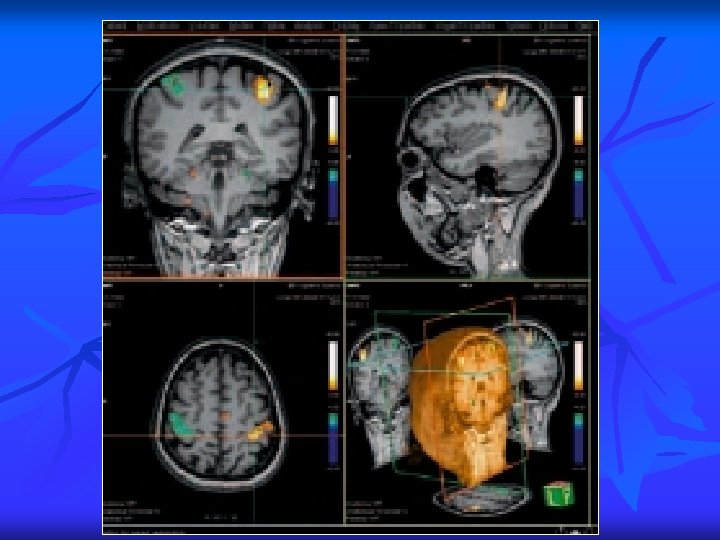

PRINCIPALES INDICATIONS 1 1. Imagerie neuroradiologique Actuellement, deux grands axes d’étude sont en pleine évolution : G Étude des aires fonctionnelles du cerveau zone motrice n aires visuelles n Étude basée sur les rapports oxy-hémoglobine, désoxy-hémoglobine donnant une véritable cartographie du cerveau

PRINCIPALES INDICATIONS 2 A Imagerie de diffusion perfusion Intérêt pour un bilan neuro-vasculaire mais aussi pour l’étude de la vascularisation des tumeurs cérébrales.